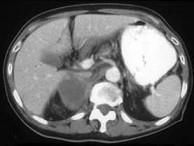

问题 男,75岁,右侧胸痛伴咯血3月余,胸部CT提示右侧中央型肺癌,请结合图像,作出诊断()

选项 A.右侧肾上腺囊肿 B.右侧肾上腺转移瘤 C.右侧肾上腺腺瘤 D.右侧肾上腺癌 E.右侧肾上腺嗜铬细胞瘤

答案 B